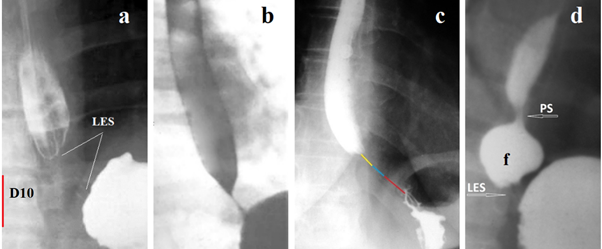

Figure 2 shows examples of radiographs of children with GERD whose analysis excludes the possibility of EA.

Figure 2 Typical radiographs showing GERD in 19 patients.

(a) A 14-year-old girl with dysphagia and vomiting. Based on radiological symptoms (dilated esophageal body, stasis of the contrast in it, a bird’s beak deformity in the EGJ) as well as on typical findings on HRM (absence EGJ relaxation), EA was diagnosed. After repeated pneumodilations of the LES dysphagia completely resolved.38

Analysis. Since the height of L-1 at this age is 2.2 cm, therefore the height of D-11 is ≈ 2 cm. What the authors called bird’s beak deformity (white arrow) is an open LES, through which the contrast agent freely fills the stomach. The length of the LES is 1 cm, which is significantly shorter than the normal LES at this age - 2.3 – 2.9 (2.45±0.11 cm). A sharp shortening of the LES indicates GERD, which is also confirmed by the presence of phrenic ampulla {a}. The esophagus is dilated just above the peptic narrowing between the two blue arrows. The diagnosis: GERD with peptic esophageal stenosis. The conclusion of HRM (absence EGJ relaxation) is erroneous, as it contradicts the obvious radiological signs: - relaxation of the LES and good esophageal emptying. The disturbance of esophageal motility was caused by peptic stenosis of the esophagus. The article does not provide information about what happened to peptic stenosis after dilatation of the LES, i.e., in another place.

(b) An 18-month-old female child was admitted with the complaints of regurgitation of feed, nonprojectile vomiting, repeated fever, and cough with occasional breathlessness for last 1 year.39 The authors diagnosed EA based on the bird’s beak appearance of the lower end of the esophagus. What the authors call “bird's beak” is an open LES with normal throughput. Analysis. The diagnosis of EA does not have a single confirmatory radiological sign, since the esophagus is not dilated, normal relaxation of the LES does not prevent the filling of the stomach. Based on erroneous interpretation of the X-ray examination, the authors diagnosed EA and balloon dilatation of the EGJ was performed. Long-term results are not shown.

(c) A 10-year-old female with Down syndrome with history of chronic daily cough and recurrent pneumonias for eight and a half years duration. Based on radiological data (diffuse dilatation of esophagus with tapering at gastroesophageal junction and small amount of contrast passed to the stomach) the authors diagnosed EA.40 Analysis. The width of the esophagus in the ampulla is 1.8 cm. Such slight dilatation of the phrenic ampulla is typical for GERD. The length of the LES from the esophagus to the air bladder of the stomach (blue arrow) is 2.1 cm, with the age norm being 1.9 – 2.3 (2.10±0.05 cm). However, the intra-abdominal part of the LES (limited by the yellow lines) is open. Only the proximal part of the LES, 1 cm long is in a contracted state. Shortening of the LES, combined with large amounts of gas and contrast material in the stomach, are also evidence of GERD. The diagnosis of EA has not been confirmed.

(d) An 8-year-old male patient. The authors diagnosed EA based on the barium examination, which revealed of an acute tapering at the gastroesophageal junction with the persistence of barium after 20 min of the swallow. Treatment by open Heller myotomy and Dor fundoplication.41 Analysis. In a horizontal position, 20 minutes after taking the contrast agent, the entire esophagus is filled with it. A width of it is 0.9 cm, i.e., significantly less than normal (1.5 cm). The length of the LES (distance between the esophagus and the stomach) is 1 cm. The age norm being 1.9 – 2.3 (2.10±0.05 cm). A significant amount of contrast agent in the stomach indicates normal evacuation from the esophagus. The narrowing of the esophagus and shortening of the LES suggests GERD with rigid esophagitis. The only sign based on which the patient was dissection of the LES, was the detection of barium in the esophagus after 20 minutes. However, on the previous radiograph, the amount of contrast material in the esophagus was significantly greater than after 20 minutes.28 This proves that after 20 minutes the esophagus was refilled with contrast material because of reflux.

(e) An 8-year-old child suffers from dysphagia and regurgitation for 2 years. Hakimi and Karimi on barium esophagogram claim LES narrowing and by arrow show bird beak sign with compensatory dilatation of the upper esophagus. Esophagomyotomy with Dor's Fundoplication was done.28 Analysis. The true height of L-1 (red line) is 1.8 cm. Therefore, the width of the lower part of the esophagus (black line) is 2.1 cm, which is slightly wider than normal (1.5 cm). The wedge-shaped continuation of the esophagus, shown by the arrow, is located at a considerable distance from the diaphragm and reaches the level of L-1. This is an opened part of the LES. Its distal part, 0.5 cm long, is in a closed state. Diagnosis: rigid reflux esophagitis with probable stenosis abdominal part of the LES.

(f) Patient ≈ 11–12-year-old.41 Hakimi and Karimi state that pre-operative contrast esophagram demonstrated achalasia and HRM demonstrated a failure of lower LES relaxation.41 Analysis. The height of D-10 is ≈ 1.7 cm. Therefore, the width of the lower part of the esophagus (black line) is 1 cm, which is significantly less than the normal width of 1.5 cm). The most distal part of the esophagus above the closed LES, 1.2 cm long (between the blue lines), is significantly narrower. It represents peptic stenosis. The length of a closed LES containing traces of a contrast agent is 1.7 cm, which is significantly shorter than the age norm - 2.3 – 2.9 (2.45±0.11cm). Narrowing rather than expansion of the esophagus, which indicates inflammation and confirms the presence of peptic stenosis, as well as shortening of the LES with traces of a contrast agent, as a sign of inflammation, allows us to conclude about GERD with reflux esophagitis, including at the LES level.